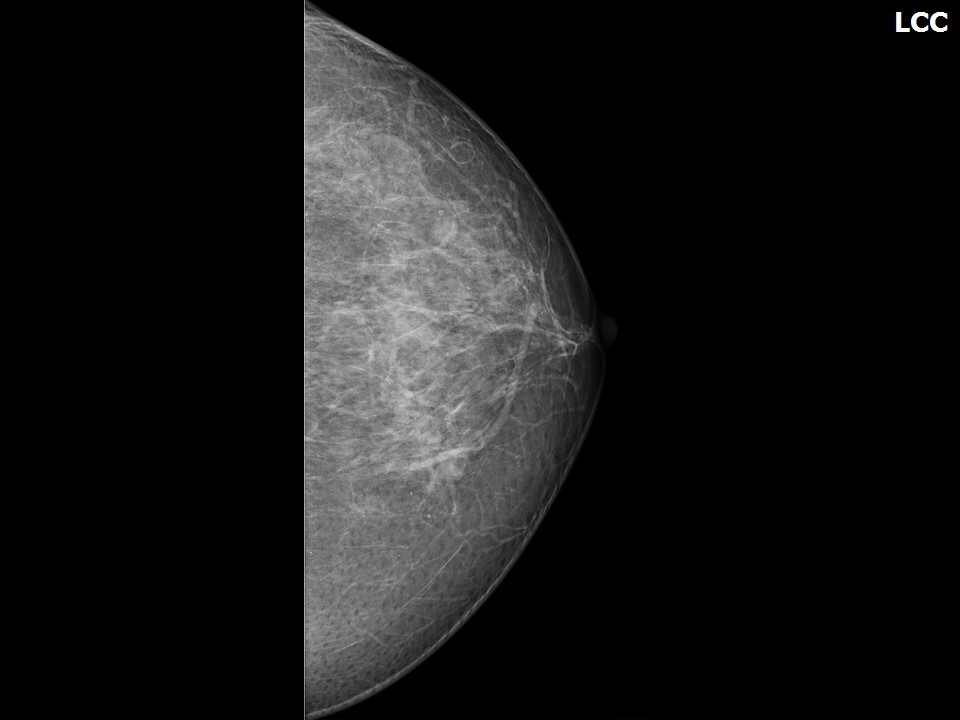

Маммография — это золотой стандарт в скрининге рака молочной железы, позволяющий выявить патологию на самой ранней стадии, когда лечение наиболее эффективно и шансы на полное выздоровление максимальны. Однако, несмотря на неоспоримую важность этой процедуры, многие женщины откладывают ее или вовсе отказываются от прохождения, оправдывая это фразой: "Мне ничего не найдут". Этот самообман, или психологический барьер, основан на ряде глубоких страхов и мифов. Понимание этих причин и осознание реальной пользы ранней диагностики — первый и самый важный шаг к преодолению этого барьера и сохранению своего здоровья.

Медицинский центр "Томакс" в Сургуте призывает женщин регулярно проходить маммографию согласно рекомендациям вашего врача или в рамках ежегодного скрининга (обычно с 40 лет). Мы используем современное рентгеновское оборудование для получения высококачественных снимков при минимальной лучевой нагрузке, что обеспечивает максимальную точность диагностики. Наш опытный персонал сделает все возможное, чтобы процедура прошла комфортно и быстро.